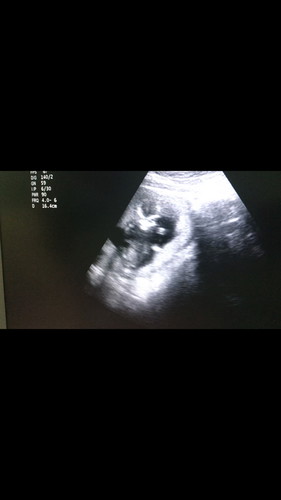

มีแม่ๆบ้านไหนกำหนดคลอดพฤศจิกายนกันบ้างคะ . เอารูปอัลตร้าซาวมาอวดกันหน่อยจ้า ของน้อง15วีคแล้ววว ?

15w ค่า กะว่าจะได้ลุ้นเพศ น้องดันนั่งก้มหน้าเลยไม่เห็นเลย กำหนดคลอด 2 ธ.ค ค่า